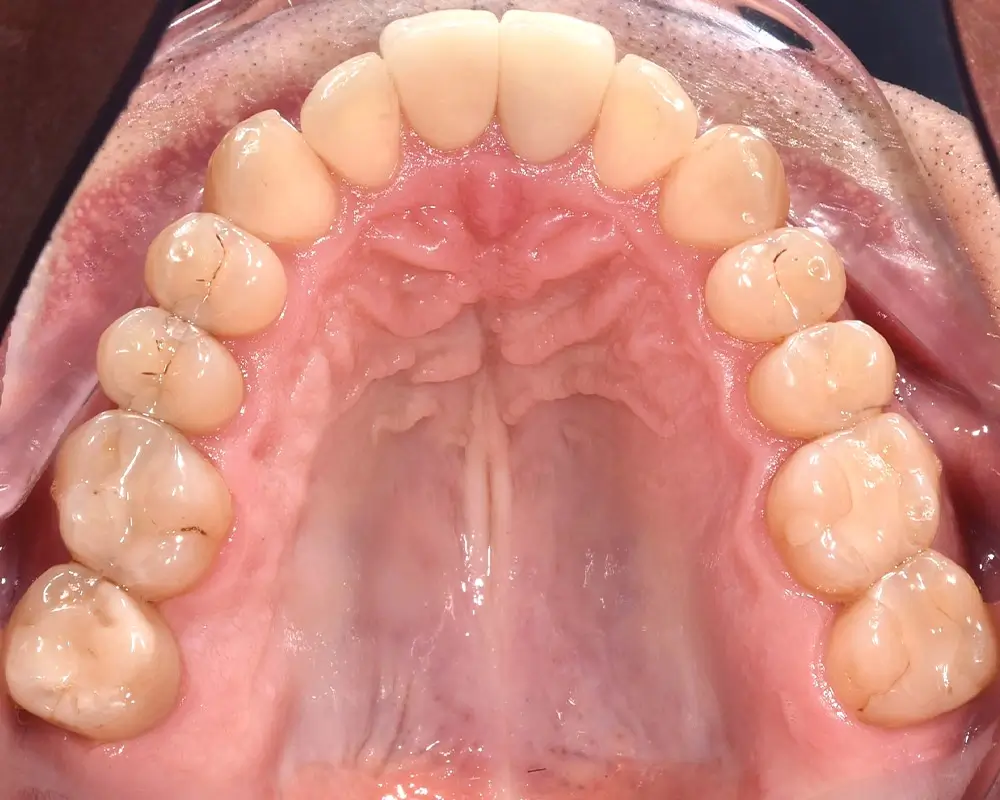

Мезиальный прикус - Кейс 7

Эффективность устранения дефекта прикуса посредством элайнеров FlexiLigner.

Результаты лечения